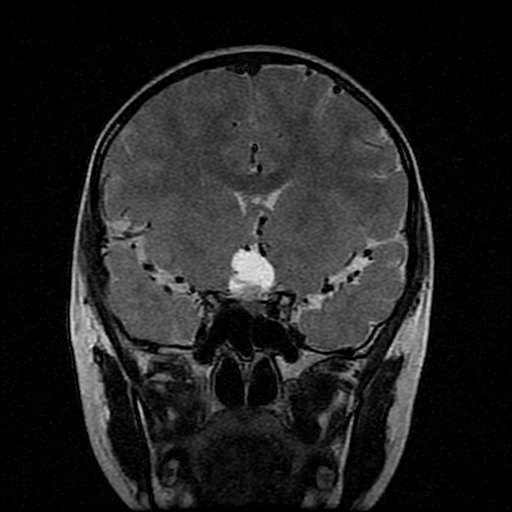

男性,12岁。反复头痛呕吐半月。脑积液无异常。病变部位ct值32hu,dwi无异常。

鞍上为主,累及鞍内,垂体受压位于鞍底。mri呈短t1、长t2信号,不太支持生殖细胞肿瘤,首考颅咽管瘤。

鞍内囊性占位性病变,t1wi、t2wi,均为高信号影。ct平扫为等密度。发病年龄较小。故首先考虑颅咽管瘤,可以做ct增强扫描